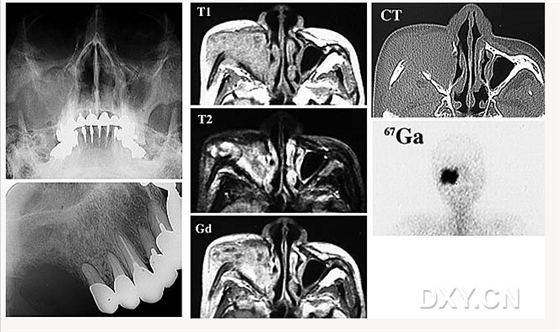

舍格倫綜合征

鼻腭囊腫

良性成牙骨質(zhì)細(xì)胞瘤